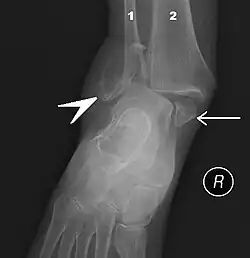

Ankle fractures may result from excessive stress on the joint such as from rolling an ankle or from blunt trauma.[21][22] Types of ankle fractures include lateral malleolus, medial malleolus, posterior malleolus, bimalleolar, and trimalleolar fractures.[21] The Ottawa ankle rule can help determine the need for X-rays.[22] Special X-ray views called stress views help determine whether an ankle fracture is unstable.

Ankle fractures are common, occurring in over 1.8 per 1000 adults and 1 per 1000 children per year.[22][23] In North America this figure increases to more than 14 in ever 10,000 patients admitted to the Emergency Room.[24] They occur most commonly in young males and older females.[22]Imaging

The initial evaluation of suspected ankle pathology is usually by projectional radiography ("X-ray").

For ligamentous injury, there are three main landmarks on X-rays: The first is the tibiofibular clear space, the horizontal distance from the lateral border of the posterior tibial malleolus to the medial border of the fibula, with greater than 5 mm being abnormal. The second is tibiofibular overlap, the horizontal distance between the medial border of the fibula and the lateral border of the anterior tibial prominence, with less than 10 mm being abnormal. The final measurement is the medial clear space, the distance between the lateral aspect of the medial malleolus and the medial border of the talus at the level of the talar dome, with a measurement greater than 4 mm being abnormal. Loss of any of these normal anatomic spaces can indirectly reflect ligamentous injury or occult fracture, and can be followed by MRI or CT.[27]